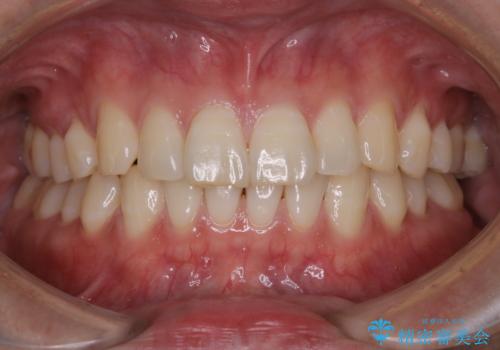

3カ月に1度のPMTCでオーラルケア

- 3カ月ごとに定期的にメンテナンスにいらしている方です。PMTC30分コースを行いました。

PMTC(保険外治療)は、毎日の歯磨きで落としきれない汚れや、タバコのヤニなどの着色も除去します。目には見えない歯と歯の間・歯肉の境目などに残っているプラーク(歯垢)もしっかり取り除きます。

- 歯を白くする目的の施術ではありません